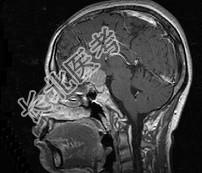

单项选择题女,32岁, 右眼视物模糊1年,加重2月, 请根据所提供图像,选择最可能的诊断是 ( )

A、鞍区转移瘤

B、鞍区海绵状血管瘤

C、鞍区动脉瘤

D、鞍区垂体瘤

E、鞍区脑膜瘤